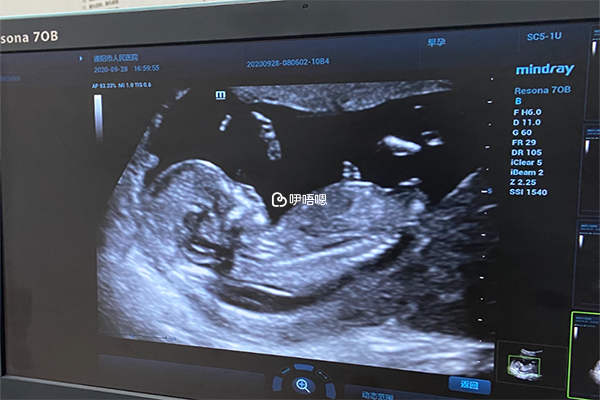

nt檢查是孕早期的第一項排畸檢查,其中nt值代表頸後部的透明帶厚度,這個厚度通常在2.5mm以下是正常的,所以nt0.7mm是正常的。如果nt值高於2.5mm,則表明有臨界風險或高風險,也意味著胎兒可能有染色體異常,此時,就需要通過無創DNA來診斷胎兒的具體情況。

網傳的nt值看生男生女的方法是,如果nt值大於1.5mm是生男孩,如果小於1mm就是生女兒。如果在1-1.5mm之間,生男孩或女孩的機率各佔一半。因此,11周+6nt值0.7mm是生女孩。